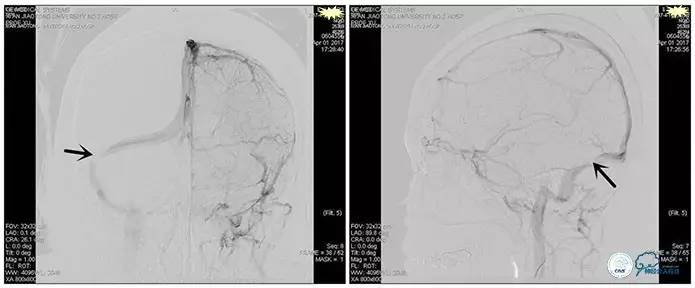

术中造影

术后造影

狭窄较前有改善

诊疗方案:为挽救视力,确定支架成形术效果,急诊行右侧横窦乙状窦狭窄球囊扩张术(6mm×20mm,Ever Cross )。

术中测压

远端压力:530mmH2O

近端压力:120mmH2O